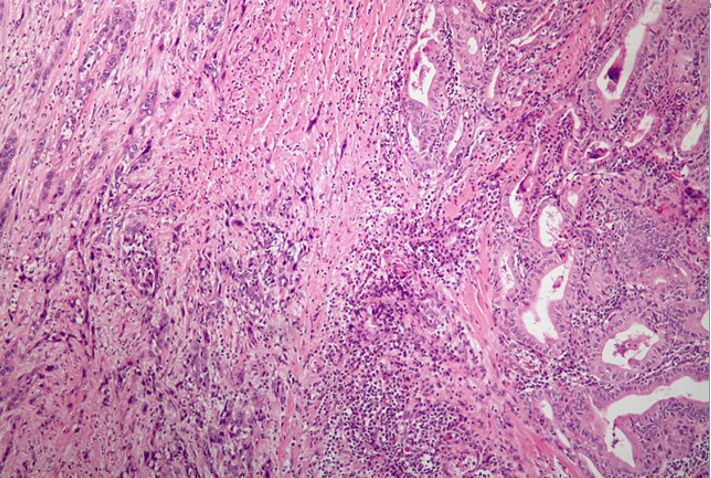

未分化型甲状腺癌组织学表现

证实这些肿瘤团周围存在肌上皮细胞,而浸润性癌组织团周围没有肌上皮